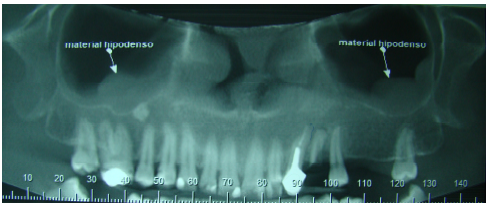

Observando a imagem abaixo e sabendo que não há sintomatologia relatada pelo paciente, marque a alternativa que corresponde ao diagnóstico radiográfico do material hipodenso:

A

Aspergilose.

B

Tumor de bainha de nervo maxilar.

C

Osteocondroma.

D

Osteoma osteóide.

E

Mucocele.